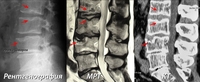

Такой уникальный комплекс хирургически-диагностического оборудования позволяет быстро и эффективно проводить операции на позвоночнике пациентам с такими болезнями, как межпозвоночная грыжа диска, стеноз позвоночного канала, перелом позвоночника и другими заболеваниями, при этом сроки госпитализации для хирургического лечения составляют от 3х до 7ми дней.